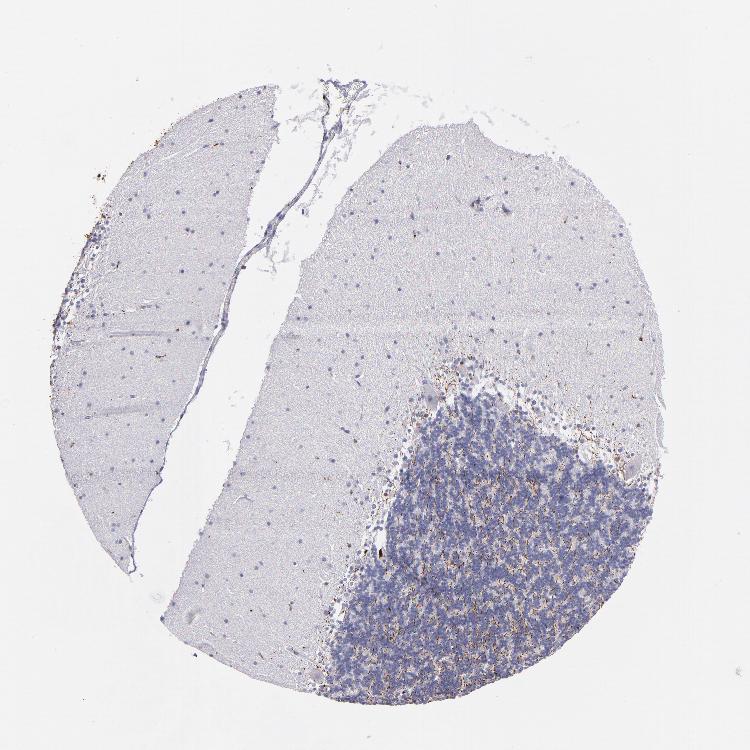

CEREBELLUM - Antibody stainingi

Antibody staining in the annotated cell types in the current human tissue is reported as not detected, low, medium, or high, based on conventional immunohistochemistry profiling in selected tissues. This score is based on the combination of the staining intensity and fraction of stained cells.

Each image is clickable and will lead to virtual microscopy that enables deeper exploration of all samples and also displays staining intensity scores, fraction scores and subcellular localization as well as patient and tissue information for each sample.

Antibody HPA002988Antibody CAB000460

Purkinje cells Not detectedNot detected

Cells in granular layer Not detectedNot detected

Cells in molecular layer Not detectedNot detected